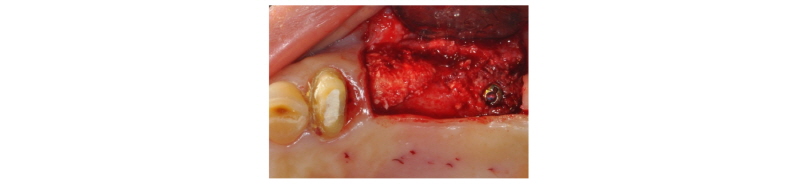

70세의 여자환자로 상악에 사용하던 부분틀니가 불편하다고 호소하시며 내원하였다. 부분 틀니의 지대치인 상악 좌측 견치 또한 보철물 하방으로 우식이 진행되어 보철물 제거후 우식치료 후 보철물을 재제작하여 장착하기로 계획하였다. 치아가 결손되어 있던 상악 좌측 소구치와 대구치 부위는 임플란트 식립(#24i-26i, 27i)을 통한 고정성 보철물 수복을 계획하였다(Fig. 19). 장기간의 부분틀니 장착으로 인해 임플란트 식립 예정 부위의 심한 치조제 흡수가 관찰되었으며 특히 소구치 부위가 가장 흡수 정도가 심하였다(Fig. 20). 전층판막 형성 후 상악 좌측 제 1 소구치 부위는 치조정에서 약 2 mm 정도의 매우 좁은 치조제 폭경이 확인되었다(Fig. 21). 먼저 상악 좌측 제 1 소구치 부위 치조정에 horizontal intraosseous groove를 작게 형성한 후 협측골에 근, 원심 양측에 vertical intraosseous groove를 형성하였다(Fig. 22). Chisel을 이용하여 협측 골판을 조금 확장시킨 다음 spreader drill (RS kit, Dentium, Korea)을 단계적으로 이용하여 충분히 확장시켜 임플란트 식립을 위한 공간을 확보하였다(Fig. 23). 분리된 협,설측 골판 사이 공간으로 Ø4.3 × 10 mm (Implantium, Dentium, Korea) 임플란트를 식립하였다(Fig. 24). 상악 좌측 대구치 부위는 상악동 거상술(측방접근법)을 시행하여 #26i, 27i : Ø4.3 × 10 mm, Ø4.8 × 10 mm (Implantium, Dentium, Korea)를 식립하였다(Fig. 25). 식립된 24i 임플란트와 협,설측 골판 사이의 gap에 합성골 (Osteon II, Xenoss, Korea)을 적용한 다음 협측 골판 상방에 콜라겐함유 합성골(Osteon II Collagen, Xenoss, Korea)을 추가적으로 적용하였고 식립된 26i, 27i 임플란트 부위의 협측골 두께가 얇아서 협측골 상방에도 콜라겐함유 합성골(Osteon II Collagen, Xenoss, Korea)을 적용하였다(Fig. 26). 골이식재 상방에 흡수성 교원질 차폐막(Collagen, Xenoss, Korea)을 피개한 후 감장절개를 통해 장력없이 봉합하였다(Fig. 27, 28). 약 10일 후 발사 시의 임상소견으로 정상적으로 치유가 잘 진행되었다(Fig. 29). 술 후 파노라마 방사선 소견으로 치조제 분할술을 통해 식립된 24i 임플란트와 상악동 거상술(측방접근법)을 시행하여 식립된 26i, 27i 임플란트가 확인되었다(Fig. 30). 4개월 치유 후 이차 수술 시 전층 판막거상 후 협측으로 충분히 증가된 치조제 폭경과 식립된 임플란트 주위에 이식한 골이 혼화되어 치유된 양상이 확인되었고 치유지대주를 연결하였다(Fig. 31). 이차 수술 후 치유가 정상적으로 진행되어 통법에 따라 보철 수복하였다. 보철물 수복 직후 방사선 사진 소견으로 식립된 24i 임플란트의 변연골 위치가 확인되었다(Fig. 32). 보철물 장착 후 1년 후 방사선 소견에서 임플란트 주위 변연골이 안정적으로 잘 유지되고 있었다(Fig. 33). 보철물 장착 4년 후 follow- up 결과 임플란트 주위 치은이 약간 퇴축된 양상을 보였으나 임상적으로 특이한 소견이 관찰되지 않았고 방사선 소견에서 임플란트 주위 변연골이 안정적으로 잘 유지되고 있음을 확인하였다(Fig. 34-36).

Fig. 28. Flap was closed with tension-free sutures. |